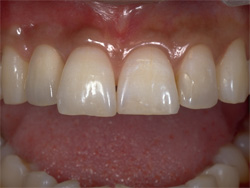

| 従来は局部的な入れ歯を用いて治療を行っていましたが、インプラントを何本か用いて治療を行います。入れ歯を固定するための金属のバネによる違和感がなくなります。 |

| 数本のインプラントにより支えられるブリッジかクラウンにより、機能と顔立ちが回復するでしょう。 |